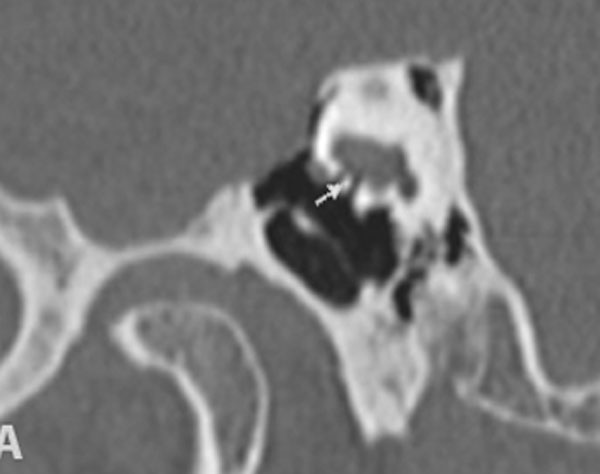

TC de alta resolução. Doente com acufenos não esclarecidos pela clínica. Aquisição reformatada no plano frontal (A) e em Pöschl (B). Em A existe deiscência da espira da cóclea (seta). Em B existe deiscência do canal semicircular superior (seta).